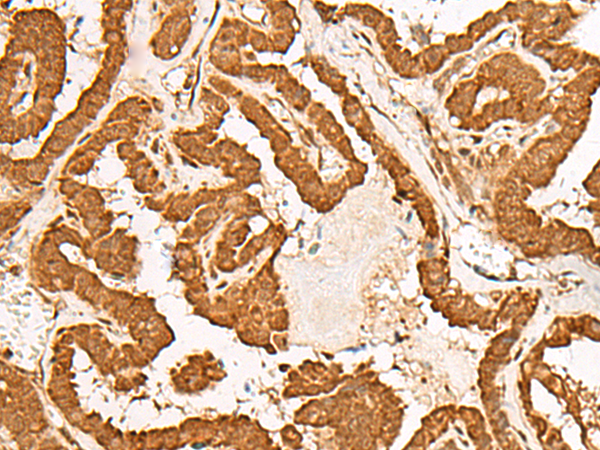

分类: 科研抗体货号: P06644别名: RAIG3; RAIG-3应用: IHC反应种属: Human, Mouse